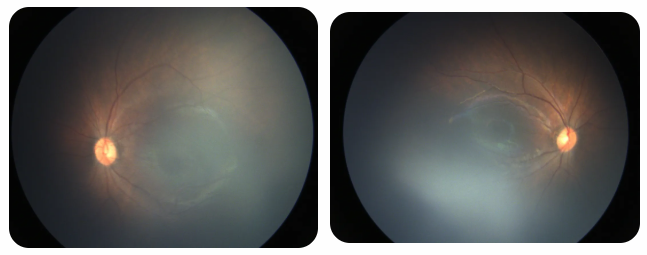

廈門眼科中心黎曉新名醫(yī)工作室曾接診一名31周出生的早產(chǎn)兒,出生體重僅1300克。由于家長缺乏篩查意識,直到孩子5個月大時眼睛仍不會追光,才前來就診。檢查發(fā)現(xiàn),患兒ROP已進(jìn)展至4B期,因纖維血管增殖牽拉導(dǎo)致視網(wǎng)膜脫離,錯過了最佳治療窗口。盡管黎曉新教授團(tuán)隊(duì)成功實(shí)施了玻璃體切割手術(shù),孩子的視力仍存在不可逆損傷。此后,孩子開啟了長期隨診復(fù)查、治療的“護(hù)眼征程”,目前其右眼矯正視力為0.6,左眼為0.8。

近期術(shù)前檢查:

早產(chǎn)兒視網(wǎng)膜病變

術(shù)后復(fù)查:

相比之下,另一位早產(chǎn)寶寶在出生5周后,生命體征穩(wěn)定之時,便在產(chǎn)科醫(yī)生的建議下轉(zhuǎn)診至廈門眼科中心。經(jīng)篩查確診為Ⅲ期ROP,黎曉新教授團(tuán)隊(duì)及時為其進(jìn)行了激光治療。半年后復(fù)查顯示,寶寶的視網(wǎng)膜血管發(fā)育正常,視力發(fā)育與足月兒童無異。